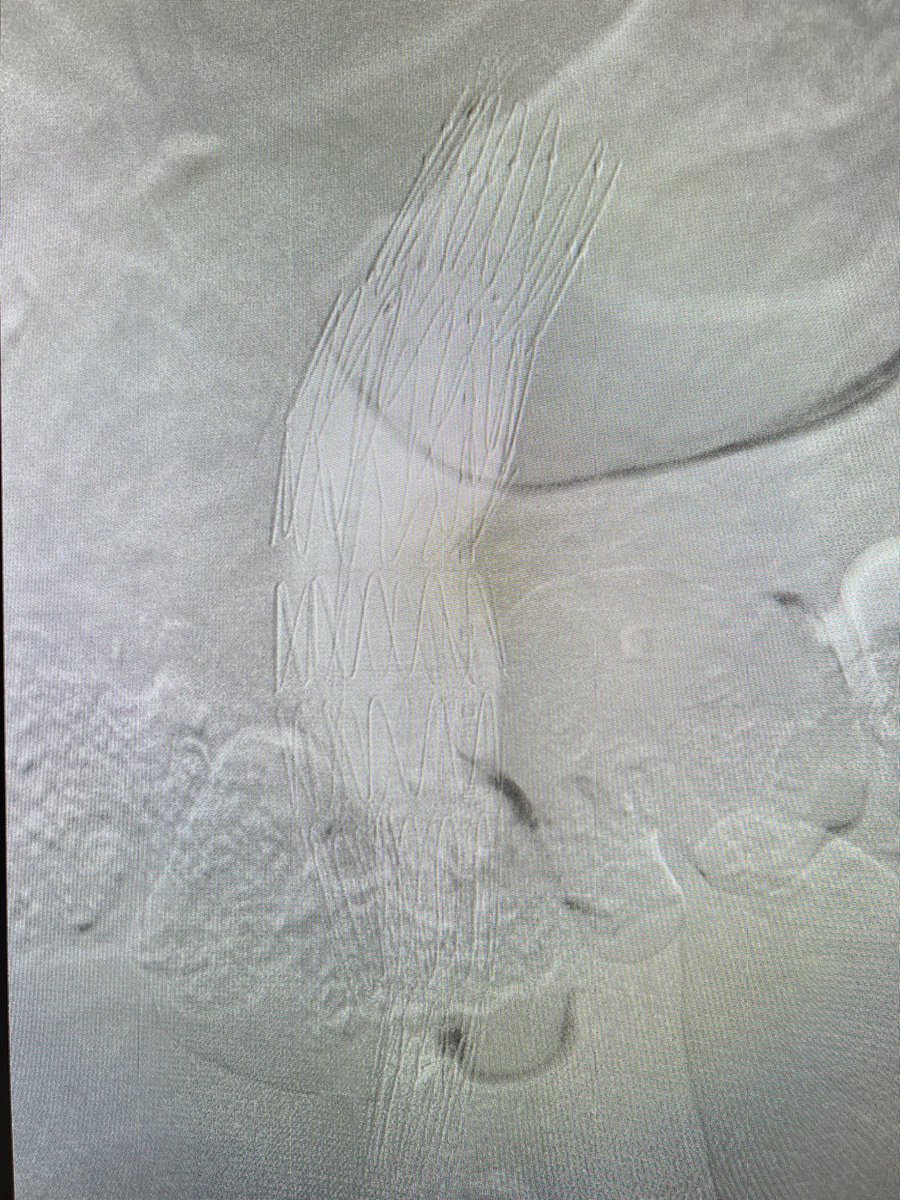

FEVAR with Diameter Reducing Ties plus 4 preloaded through-and-through wires for a small lumen case. Access from above. #AortaEd @gracemulatti @paulomenezesf @cfbechara @fonseca_alan5 @AndrePoci

This was a special case. Retired cardiologist! 95y! Didn’t want any intervention till becomes symptomatic! Minimalist aproach! Now he will get to 100y! Tks to my friend @vinesteves that help us! @cleversonzuk @w_jyg @KPujdak @evandrofilhobr @sbhci @acasatavi